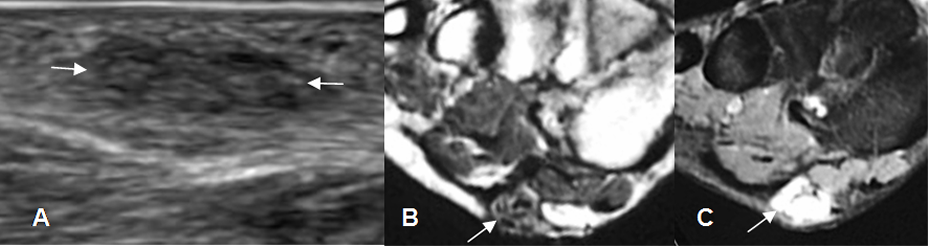

Fig 112 A. Fbromatosis.

Ecografia en corte sagital. Imagen ovalada, hipoecoica y parcialmente definida, en los tejidos blandos superficiales de la palma de la mano, por encima de los tendones flexores y compatible con fibromatosis.

Fig 112 B. Fibromatosis.

A: RM axial en T1 y B: RM axial en T2. Presencia de tejido inflamatorio agudo hipointenso en T1 e hiperintenso en T2, que rodea los tendones flexores, a nivel de la muñeca.

Fig 112 C. Fibromatosis.

A: RM coronal en T1 y B: RM coronal en STIR. Tejido inflamatorio agudo hipointenso en T1

e hiperintenso en STIR, que rodea los tendones flexores, en la muñeca y la palma de la mano.